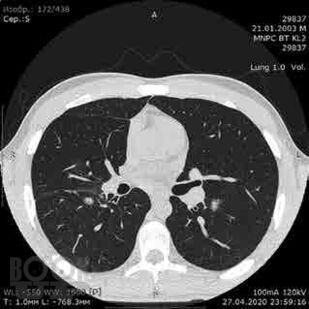

Сборник включает вызвавшие наибольший интерес аудитории лекции и доклады на различных научно-практических конференциях в 2019–2020 гг. по актуальным проблемам пульмонологии и аллергологии детского возраста, таким как: современные методы диагностики и лечения, острые и хронические инфекционно-воспалительные и аллергические заболевания органов дыхания, муковисцидоз, туберкулез органов дыхания, Covid-19, а также страницы истории, различные другие информационные материалы. Ежегодник адресован практикующим детским пульмонологам и аллергологам.